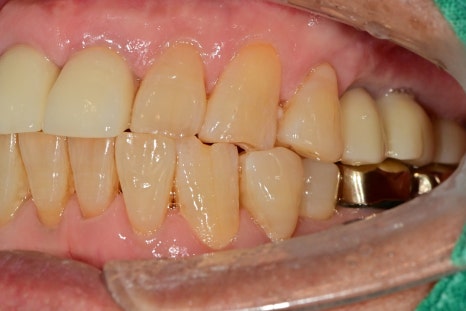

발치 후 치아 상실 부위 임플란트 수술 후 사진입니다.

발치된 치아를 보면 치아가 갈라져 있는 것을 확인할 수 있습니다.

중장년층의 남성분으로 평소 저작력이 매우 강하시지만

한쪽 어금니의 상실로 모든 힘이 나머지 치아에 무리를 일으켜 파절된 것으로 보입니다.

치아가 오랜 기간 없던 부위의 뼈 밀도가 낮아

심한 마모에 의한 증상 있는 치아의 신경치료 및 보철 치료까지 완성을 했습니다.

임플란트 보철 완성 그리고, 교합력의 분산

비어있던 어금니 공간이 모두 회복이 되었습니다.